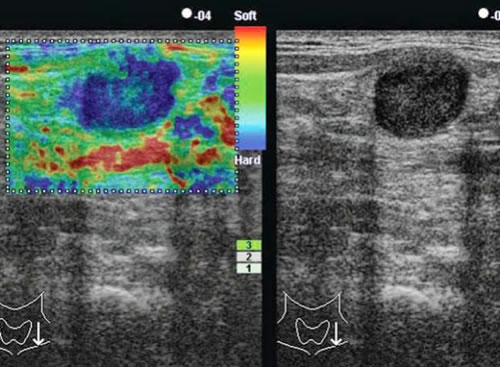

L’immagine elastografica viene espressa con una scala cromatica (per convenzione, rosso: elasticità elevata; verde: elasticità intermedia; blu: assenza di elasticità) e con dei valori numerici che sono espressione di differenti gradi di elasticità.

I colori utilizzati possono essere diversi a seconda del tipo di ecografo e del software utilizzato, ma la scala di colori solitamente varia dal rosso/verde per gli elementi dotati di una maggior deformabilità (noduli soffici) al blu per quelli con minima o nulla distorsione (noduli duri ed anelastici).

L’apparecchiatura utilizzata (Hitachi Preirus) fornisce contemporaneamente l’immagine ecografica real time nella parte destra dello schermo e l’immagine elastografica sovrapposta a quella ecografica nella parte sinistra dello schermo.

Questo accorgimento permette di controllare costantemente che il nodulo esaminato sia correttamente compreso nel piano di scansione durante la compressione.

Al fine di valutare la durezza dei noduli, il pattern elastosonografico di ciascun nodulo viene confrontato con quello del tessuto tiroideo circostante ed in base a questo le lesioni possono essere classificate in diverse classi di durezza (classi di durezza o di elasticità, Elasticity Score, ES).

Alcuni utilizzano una classificazione in 3 o in 5 classi di durezza, ma la classificazione attualmente più utilizzata è quella in 4 classi di durezza che prevede che:

- ai noduli che presentano elasticità in tutta l’area esaminata (nodulo omogeneamente verde) si attribuisca un Elasticity Score 1;

- ai noduli che presentano elasticità nella maggior parte dell’area esaminata (nodulo prevalentemente verde) si attribuisca un Elasticity Score 2;

- ai noduli che presentano durezza nella maggior parte dell’area esaminata (nodulo prevalentemente blu) si attribuisca un Elasticity Score 3;

- ai noduli completamente anelastici (nodulo omogeneamente blu) si attribuisca un Elasticity Score 4.